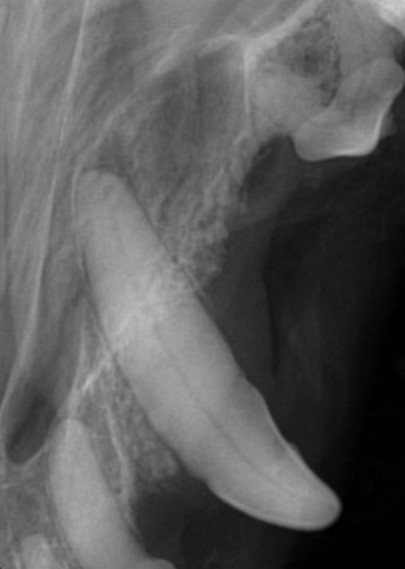

Figure 3: Canine tooth six months after vital pulp therapy. A dental bridge has formed just below the dressing material at the fracture site and the pulp canal has narrowed indicating the tooth is vital and healthy

Figure 4: Canine tooth with a deep periodontal pocket before guided tissue regeneration \

Figure 5: Canine tooth after guided tissue regeneration. The periodontal pocket has been populated with bone and a new periodontal ligament space is present indicating regeneration of the periodontal ligament. (First premolar tooth has been extracted)